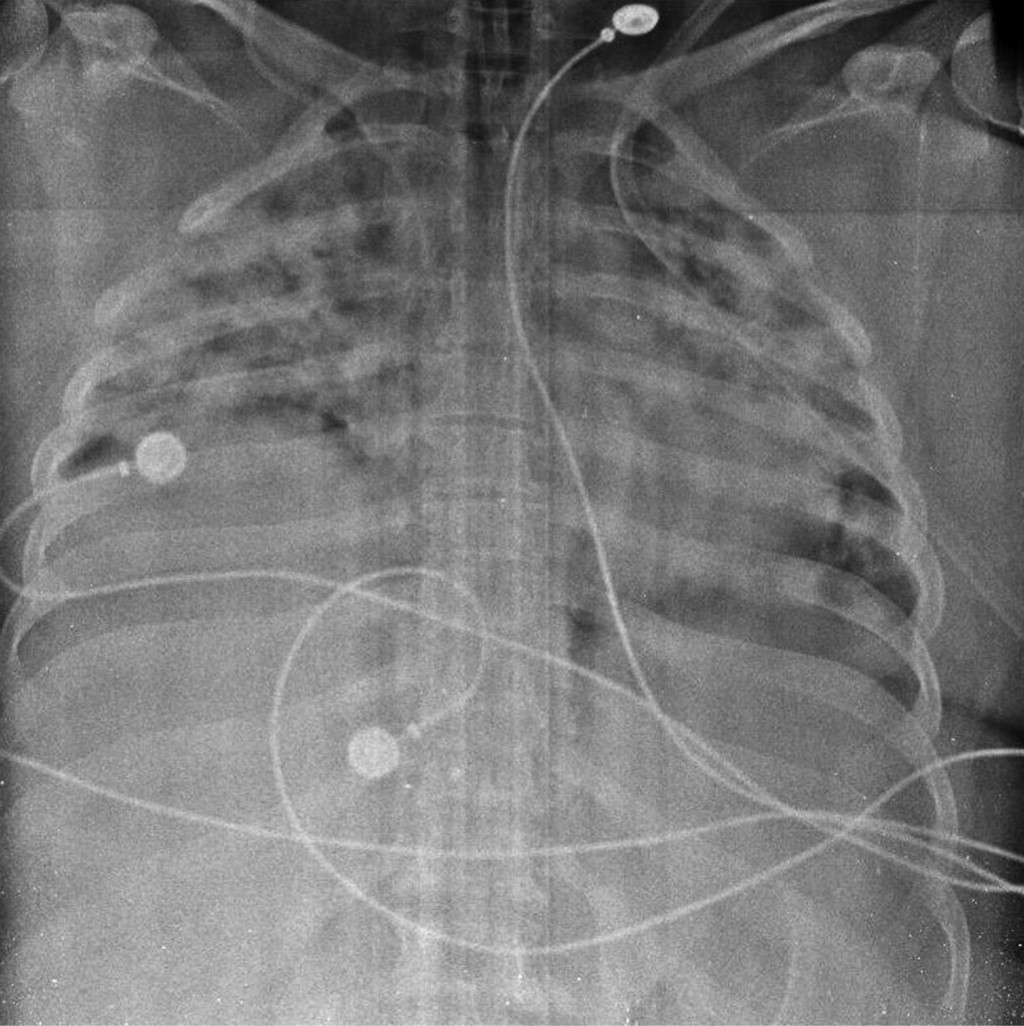

Figure 1